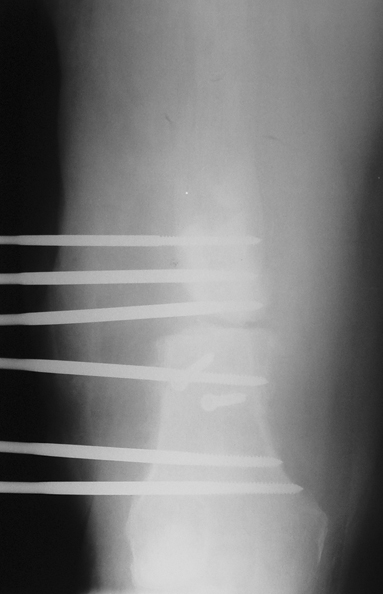

Appropriate radical debridement necessitates excision of all necrotic bone and soft tissues, and frequently causes instability at the involved extremity. The remaining bone and soft tissue defect has to be fixed and reconstructed. The distraction osteogenesis method of Ilizarov is used successfully for achievement of union, correction of the deformity, elimination of limb length inequality and reconstruction of segmental bone defects.

The duration of external fixation (external fixation index) depends on the amount of distraction required, and the extremity is prone to complications during this period. After the distraction phase is completed, the external fixator remains in place during the consolidation phase, which lasts twice as long as the distraction phase; but this period is hardly tolerated. If the external fixator is removed before sufficient consolidation is achieved, fractures, deformity and shortness will be the result. In our department, ‘lenghthening over nail’ method is used in order to decrease the external fixation index and increase patient comfort and activity level. In this method, the intramedullary nail is statically locked after the completion of the distraction phase, and external fixator is removed. The extremity is stabilized by the intramedullary nail during consolidation phase. In this way, complications due to long external fixation index or early removal of the external fixator are avoided.